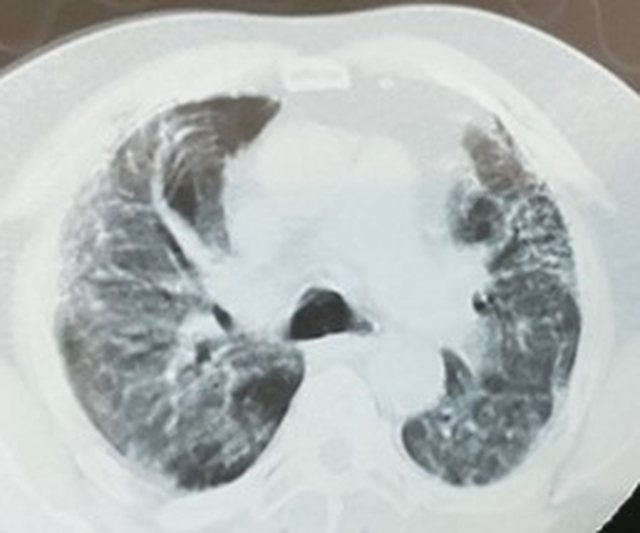

Mjeku ka kërkuar shmangien e grumbullimeve për fushatë, ndërsa ka publikuar edhe CT-Scannerave, të disa individëve të rinj që kanë humbur jetën nga covid.

“Grumbullimet në takimet elektorale, në ndodhitë familjare, në mjetet e transportit publik apo edhe në mjediset e shkollave, si edhe mungesa e zbatimit të masave të higjenës në mjediset kolektive, po ndikojnë dhe do të vijojnë të ndikojnë në shtimin e rasteve të infektimeve nga Sars-Cov2/Covid-19….FUSHATA ELEKTORALE për zgjedhjet e parlamentare të 25 Prillit 2021, për asnjë dekikë nuk duhet të zbehë përditshmërinë e punës dhe përpjekjeve në përballjen me Sars-Cov2/Covid-19….JO PËR TË FRIGUAR grup moshat nën 40-45 vjeç, por për t’i ndërgjegjësuar ato i kam bashkëngjitur këtij postimi imazhe të CT-Scannerave, të disa individëve të këtyre grupmoshave që nuk kanë mundur t’a fitojnë betejën e përballjes me këtë “flamë”….Përpiquni të qëndroni sa më larg ndikimeve jo dobiprurëse të Gjithologëve dhe Anal-istëve, që fatkeqsisht kanë mbirë kudo në TV apo në Shtypin e shkruar dhe në Rrjetet sociale…JU DUAM dhe jo pak rrezikojmë edhe jetët tona në vijën në parë, që me Punën, Përkushtimin dhe Profesionalizmin tonë të mundet në MIRËBESIM dhe MIRËKUPTIM, të ngadhnjejmë në këtë “luftë me armikun e padukshëm”….Together forever!!!”, shkruan Kalo.